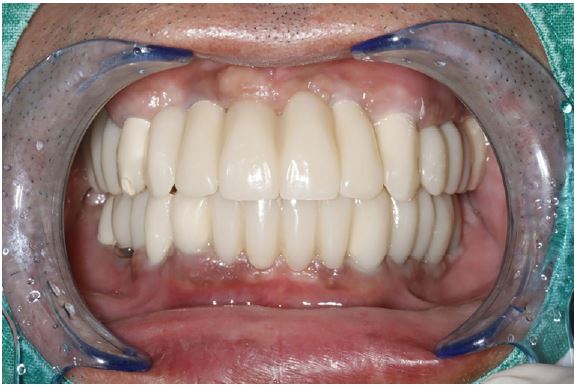

Provisional fixed prostheses were fabricated without any changes in vertical dimensions. This is a result of superimposition of the intraoral scanning data using implant scan bodies with previous scanning data. Intraoral scanning of the entire jaw at the abutment level was performed after confirming osseointegration in the right mandibular first molar region. After scanning the upper and lower jaws at the abutment level, the same vertical dimension of the provisional prosthesis was applied to the final prosthesis: (a) the left inter-occlusal relationship was scanned with the 3-piece PMMA restoration inserted on the right side, and (b) the right bite was scanned with the PMMA restoration inserted on the left side.

The treatment was completed without any discomfort after delivery of the final prosthesis because the vertical dimension or occlusal surface shape of the prosthesis was exactly the same as that of the provisional prosthesis (Figs. 10 and 11).